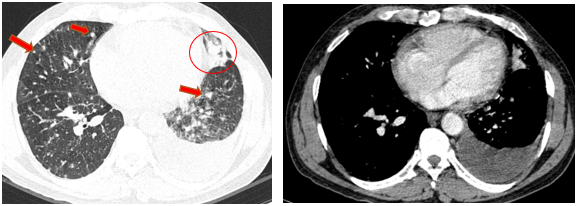

-         Chụp cắt lớp vi tính lồng ngực (08/2025): Khối rốn phổi trái ôm quanh nhánh phế quản thùy dưới trái kích thước 28x26mm, dày tổn chức kẽ vách liên tiểu thùy và nhiều nốt đặc lan tỏa khắp nhu mô, đường kính <7mm. Màng phổi trái có vài nốt đặc ngấm thuốc nốt lớn nhất kích thước 17x15mm  Khoang màng phổi trái có dịch dày 54mm. Nhiều hạch to trung thất, rốn phổi hai bên và hố thượng đòn có hoại tử trung tâm, hạch lớn nhất kích thước trục ngắn 22mm.

Hình 02: Khối rốn phổi trái ôm quanh nhánh phế quản thùy dưới trái kích thước 28x26mm, dày tổn chức kẽ vách liên tiểu thùy và nhiều nốt đặc lan tỏa khắp nhu mô, đường kính <7mm.

Hình 03: Màng phổi trái có vài nốt đặc ngấm thuốc nốt lớn nhất kích thước 17x15mmKhoang màng phổi trái có dịch dày 54mm

-         Chụp cắt lớp vi tính lồng ngực (11/2025): Màng phổi vùng rốn phổi trái dày,dày tổ chức kẽ vùng ngoại vi đáy phổi hai bên. Màng phổi trái có vài nốt đặc ngấm thuốc nốt lớn nhất kích thước 17x15mm. Khoang màng phổi hai bên không có dịch – khí (Tổn thương giảm đáng kể so với phim chụp 08/2025). Trung thất, rốn phổi hai bên, hố thượng đòn trái có vài hạch, hạch lớn nhất kích thước 12x6mm. Vài nốt đặc xương rải rác thân đốt sống, các cung xương sườn hai bên.

Hình 08: Khối u đáp ứng gần hoàn toàn, chỉ còn tổn thương dạng kính mờ, các tổn thương dày tổ chức kẽ vách liên tiểu thuỳ, nốt đặc rải rác 2 trường phổi cũng gần như biến mất.

Hình 09: Không còn tổn thương tràn dịch màng phổi trái trên phim chụp

+      Khối u rốn phổi trái thoái triển gần hoàn toàn, các tổn thương dày tổ chức kẽ vách liên thùy và nốt đặc rải rác hai trường phổi phổi giảm rõ

+      Không còn tràn dịch màng phổi.